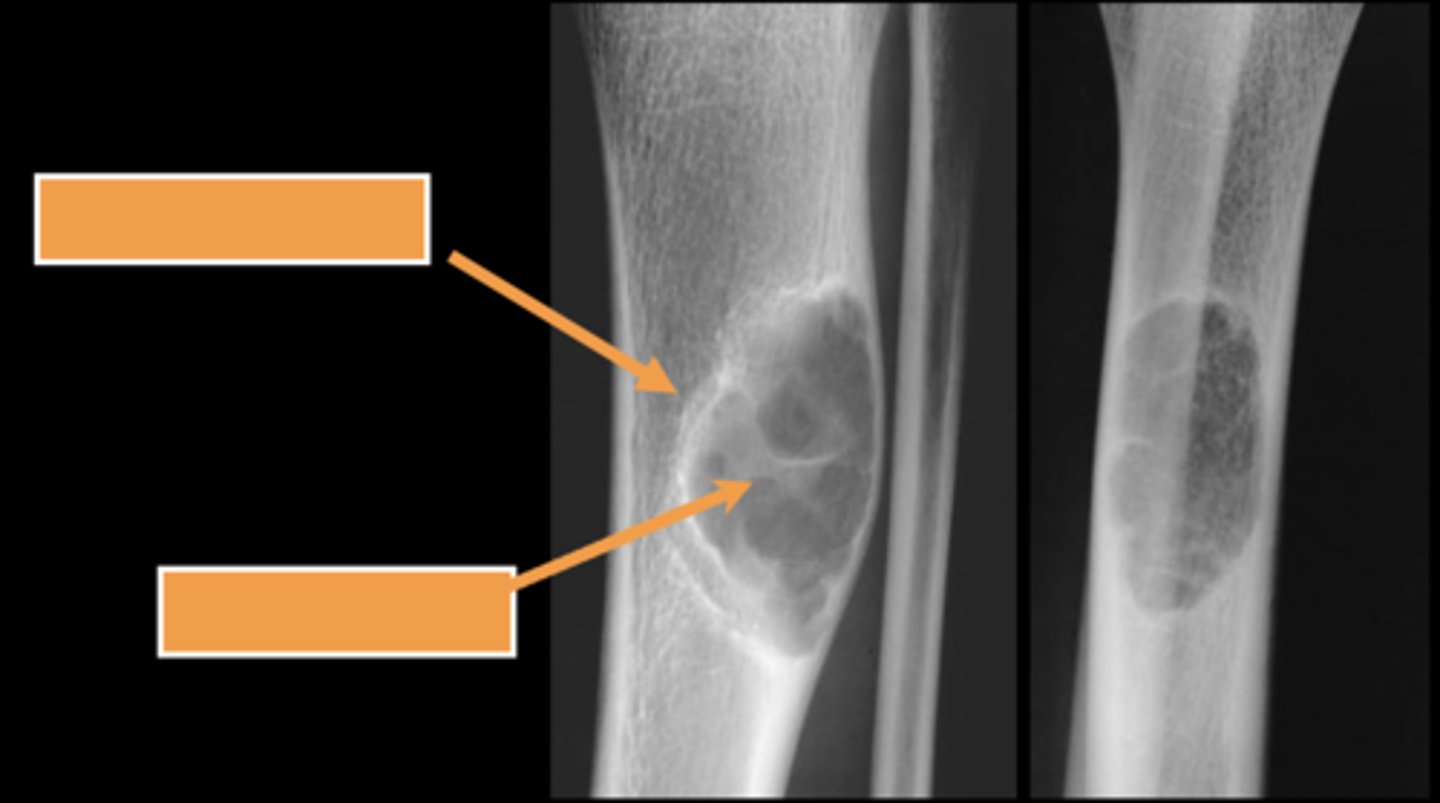

Geographic bone blister

ID radiographic feature of non-ossifying fibroma indicated by top arrow

<p>ID radiographic feature of non-ossifying fibroma indicated by top arrow</p>

Septations

ID radiographic feature of non-ossifying fibroma indicated by bottom arrow

<p>ID radiographic feature of non-ossifying fibroma indicated by bottom arrow</p>

Pathologic fracture

ID radiographic feature of simple bone cyst indicated by the top arrow

<p>ID radiographic feature of simple bone cyst indicated by the top arrow</p>

Fallen fragment sign

ID radiographic feature of simple bone cyst indicated by the bottom arrow

<p>ID radiographic feature of simple bone cyst indicated by the bottom arrow</p>

New cards

Fallen fragment sign (10%)

- Cortex broke off

- Pathognomonic

<p>- Cortex broke off</p><p>- Pathognomonic</p>